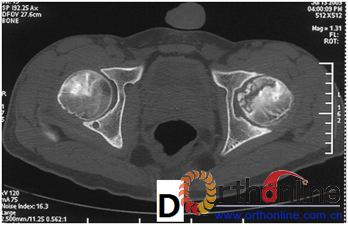

2. 依据SARS后ARCO分期Ⅰ期的ONFH患者(自然进展组)初次普查时的MRI或CT片,选用冠状位正中层面的T1WI(MRI)图像或冠状位二维重建的正中层面的(CT)图像,根据坏死灶占据外侧柱情况分为三型。Ⅰ型:坏死灶占据中央及内侧柱,外侧柱完全保留;Ⅱ型:部分外侧柱被坏死灶占据,部分保留(至少外侧皮质保留);Ⅲ型:坏死带穿透股骨头骨髓与外侧皮质,外侧柱无存留。(图2)

图2 依据股骨头外侧柱存留情况,股骨头坏死的分型。(图2-1)分为Ⅰ型(外侧柱全部存留)(A)MRI图像显示;(B)7年后CT显示股骨头仍未塌陷;(图2-2)Ⅱ型(外侧柱部分保留)(A)MRI显示外侧皮质存留;(B)4年后CT显示股骨头仍未塌陷;(图2-3)Ⅲ型(坏死带穿透股骨头);(A)MRI显示坏死带;(B)2年后股骨头塌陷

Fig 2 According to preservation of the lateral pillar, the necrosis was divided into three types. (Fig 2-1)Type Ⅰ: Whole lateral pillar preserved (A) MRI showing; (B) no collapse occurred seven years later by CT showing. (Fig 2-2)Type Ⅱ: Preservation of the partial lateral pillar, (A) MRI showed the preservation of the lateral cortical bone; (B) no collapse of the femoral head four years by CT. (Fig 2-3)Type Ⅲ: the necrotic line pass through the cortical bone and bone morrow ;(A) MRI showed the necrotic line; (B) collapse of the femoral head occurred two year later.